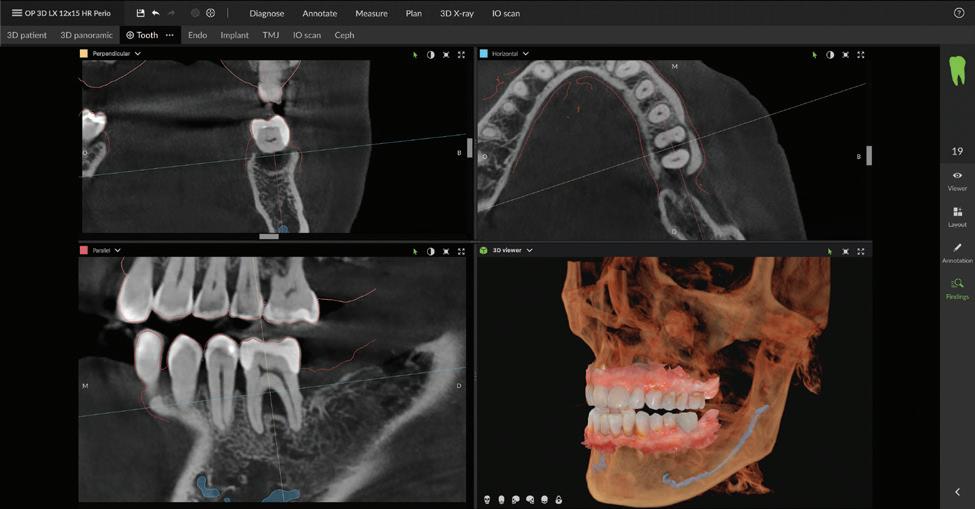

Simplify and expand your 3D diagnostics with the new ORTHOPANTOMOGRAPH™ OP 3D™ LX

Built on OP 3D technology, the OP 3D LX imaging platform expands your 3D diagnostic capabilities with a wide range of clinical applications that support your evolving practice and enhance diagnostic confidence.

Consistent, high-quality images

Seamless integration with new DTX Studio™ Clinic software

P acked with AI-assisted software features, DTX Studio™ Clinic complements OP 3D LX in numerous ways—for example, correcting patient positioning errors and detecting

landmarks, annotating mandibular nerve canals, tracing patientspecific panoramic curves for mandible and maxilla and merging CBCT and intraoral scan data for improved implant planning. These intuitive award-winning software features support a more efficient workflow allowing you to spend less time in the software and more time with your patient.